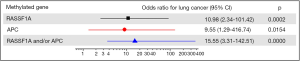

Methylation and risk of lung cancer

Figure 5 showed the results of the correlation between number of methylated genes and risk of lung cancer. The diagnostic value of each gene was graphed as a forest plot. Methylation of either RASSF1A or APC in plasma was association with the odds of lung carcinoma. The estimated odds ratio for diagnosis was 15.55 with paired methylated RASSF1A and APC (P=0.000).